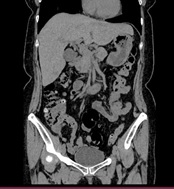

胸部CT画像 腹部CT画像

CT検査には、そのまま検査台に寝ていただき撮影する単純CTと造影剤を用いた造影CT検査があります。基本的には単純CT検査を行った後、より詳細に観察したい場合や血管などを観察する場合に行います。造影CT検査は肘(ひじ)のあたりに針を刺し血管内(静脈)に造影剤を入れて撮影します。

単純CT画像 造影CT画像 MPR画像